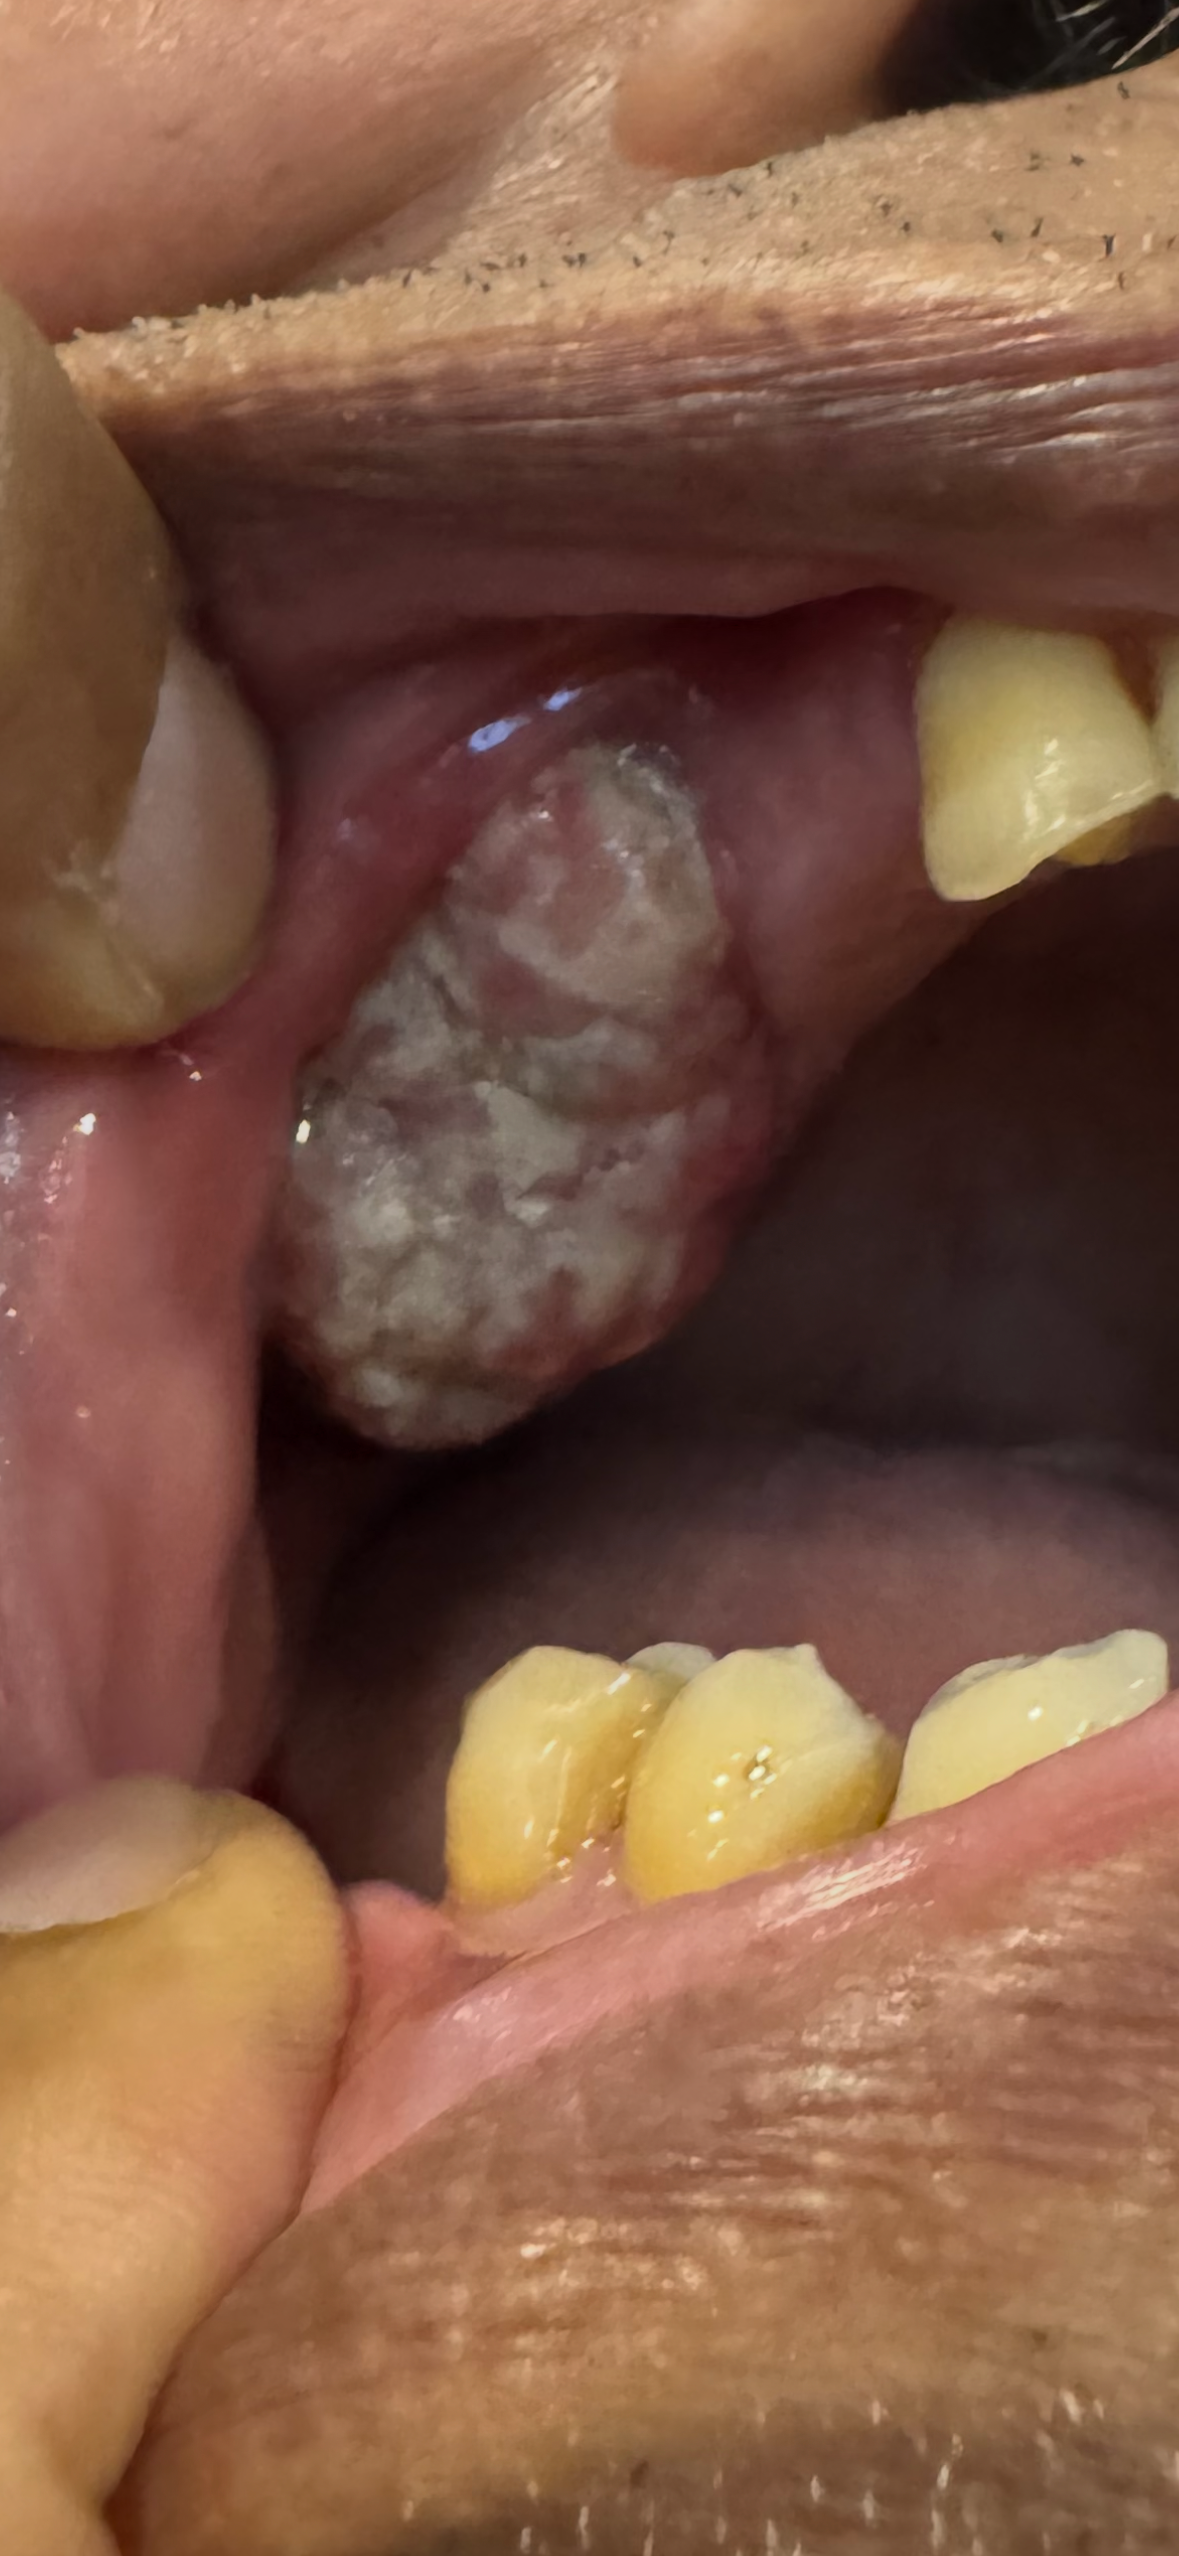

I was diagnosed with gum cancer (massive maxillary mass / 5.4 cm long / tumor) at UCLA Ronald Reagan Medical Center by Head and Neck Surgeon Dr. Keith Blackwell, MD, and Oral Surgeon/UCLA Oral and Maxillofacial Surgeon Dr. Pafam Afzali, who performed surgery to remove the tumor, almost the entire upper jaw bone, and gum on July 28, 2025. I was hospitalized for a month.

I've been going through a lengthy journey of cancer treatments, radiation, chemotherapy, and also facial reconstruction. I really need your financial support to go through this lengthy journey to survive until the end of the journey. I would really appreciate your support.